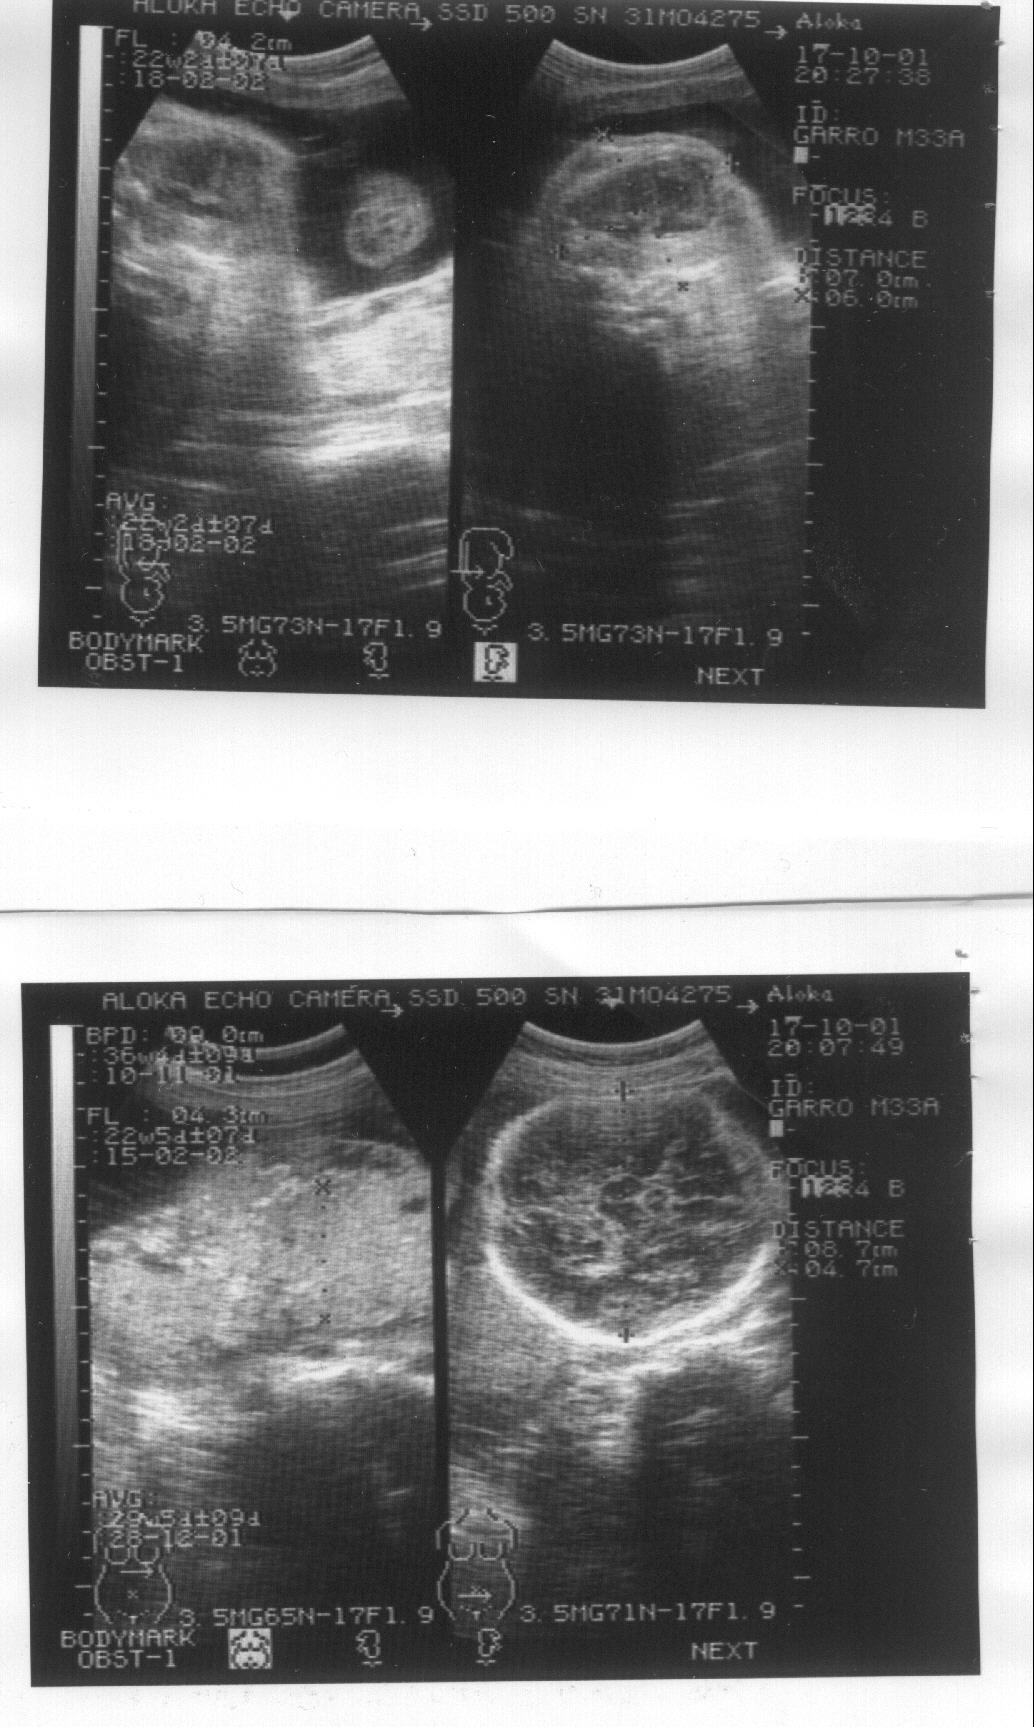

Un caso de osteogénesis imperfecta letal. Octavo mes de embarazo. Imagen 1/4

Imagen de la ecografía